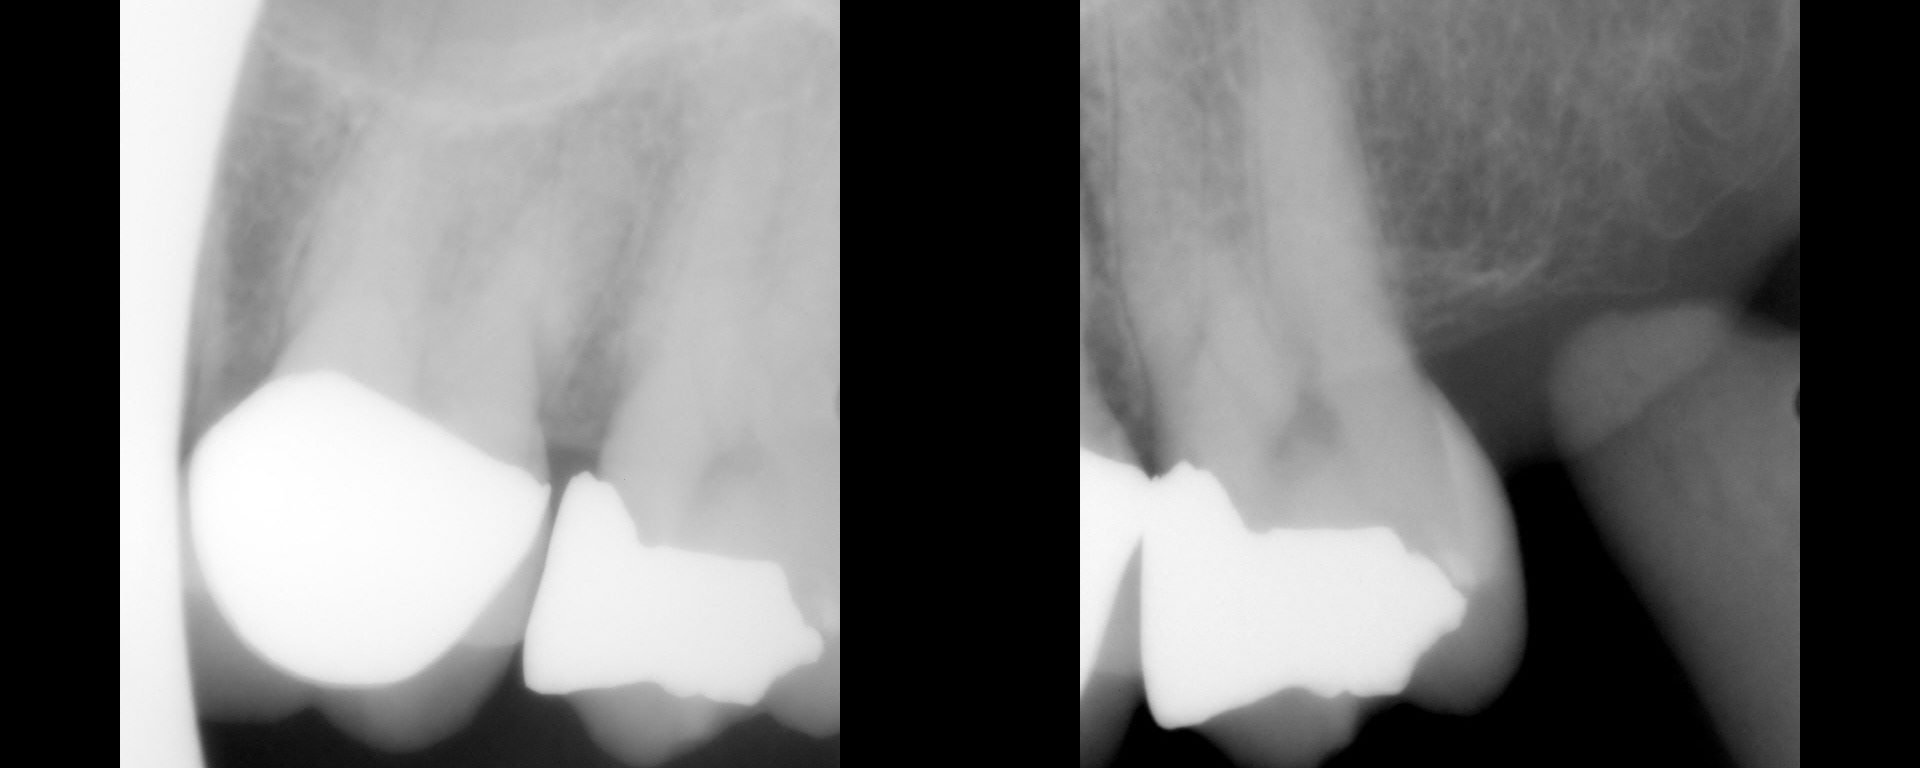

Struggling with elevated margins

Hi Gary, What you want to do is flush-up first, then do the DME. Here…it looks like there is a distal concavity that isn't flushed up. Then, you put in the finish line, but the finish line is relative to the "not-flushed-up" direct margin. You don't need the teflon tape…although that's fine…the objective is not […]